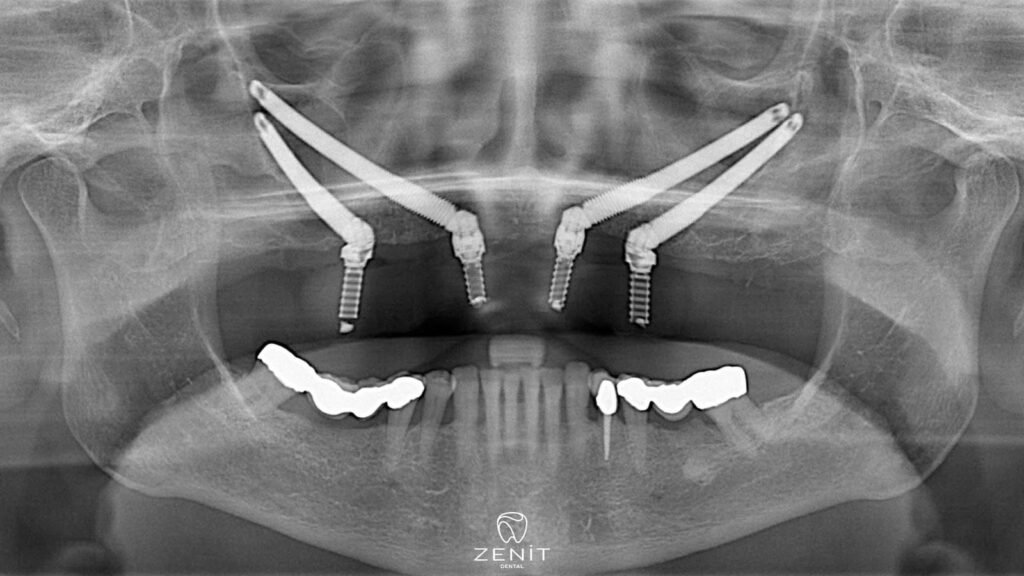

Zygoma implants offer an excellent alternative for patients with inadequate jawbone and provide a revolutionary treatment in the facial area. These special implants, unlike traditional implants, are placed in the zygomatic (zygoma) bone instead of the upper jaw bone. Since the zygomatic bone has a denser and stronger structure than the jawbone, zygoma implants can be safely placed in this area. Thanks to zygoma implants, even patients with advanced bone loss can achieve aesthetically and functionally satisfactory results.

Zygoma implants placed in the cheekbone, unlike other dental implants, are placed not in the jawbone, but in the area called zygomatic bone, which is located in the middle of the face and has a very solid structure. The zygomatic bone has a denser structure than other bones and bone loss usually does not occur. Thanks to this feature, zygoma implants offer a safe and effective solution to patients with jaw bone deficiency.

- Implant Placement: Zygoma implants are placed in the cheekbone instead of the upper jawbone. The surgeon works with high precision when placing the implants, because reaching the zygomatic area and placing the implants in the correct position requires great care.